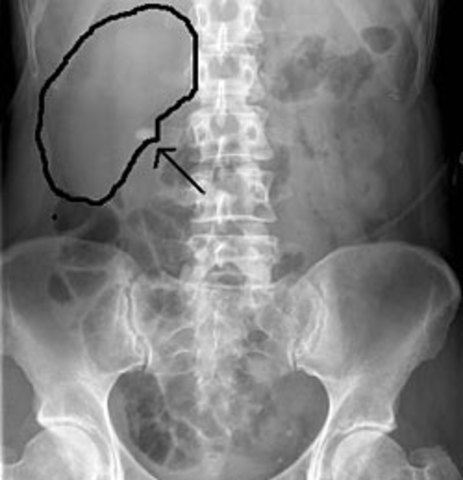

My First Kidney Stone

When I was in the 5th grade and i was havng sudden pains every once in a while by my side. I had those pains foe about 2 weeks but the funny thing is that i would lay a certain way and it would go away. But one night it was not the case i woke up in a screaming pain crying and thowing up every were, and i could not even walk to the car or to the emergecy room.